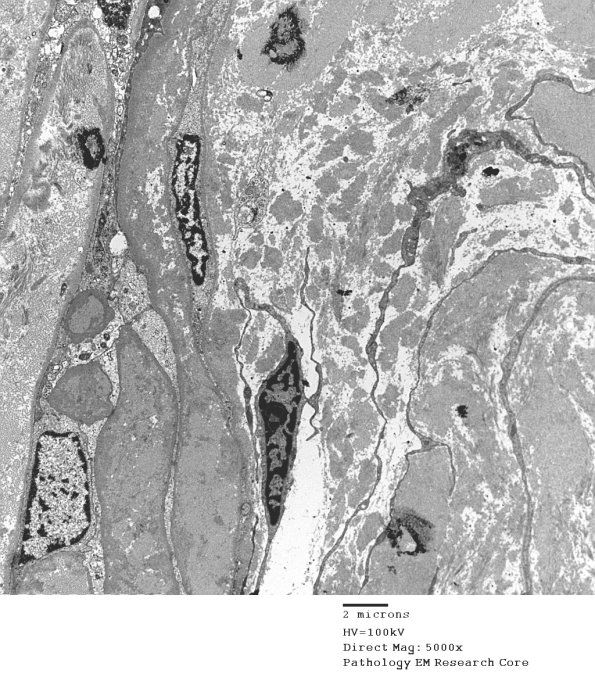

1B10,11 Notice that this RB extends from the perineurium (arrowheads, 1B11) to solid admixtures of oxytalan and collagen (arrow). (electron micrographs)